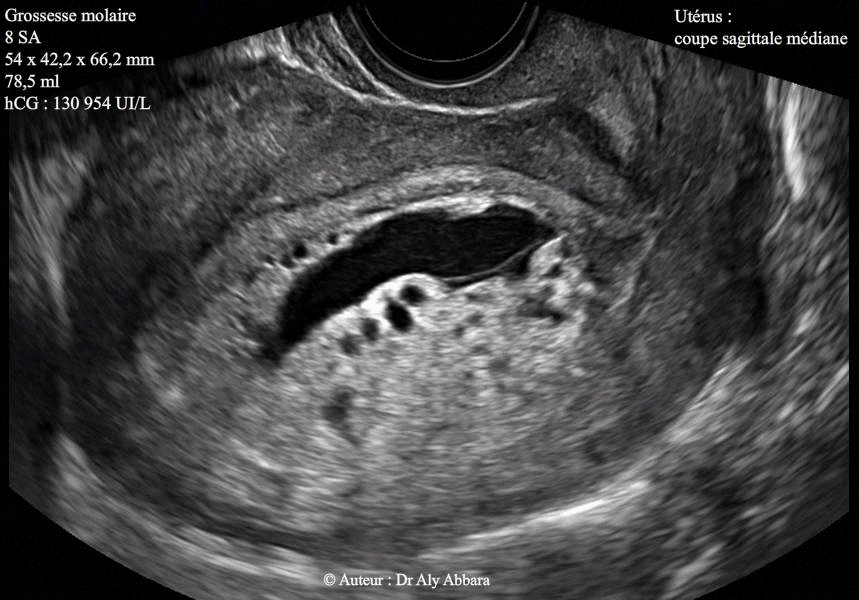

• Il s'agit d'une grossesse molaire complète découverte fortuitement lors d'une consultation pour la prise en charge d'une grossesse débutante, sans aucune manifestation clinique en dehors du retard de règles de 6 semaines (= 8SA).

• L'échographie par voie endovaginale montre une cavité utérine occupée par une structure tissulaire, hétéro-échogène, plutôt vésiculaire et sans aucun élément anatomique embryonnaire ou fœtal reconnaissable, mais le sac amniotique est présente.

Le volume de cette môle hydatiforme a été évalué à 78,5 ml (54 x 42,2 x 66,2 mm de dimensions).

Les ovaires sont normaux (sans formations kystiques lutéiniques).

• Biologiquement, le taux de β-hCG plasmatique était très élevée, à 130 954 UI/ml.